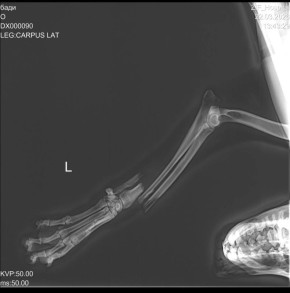

Служба спасения для кота. Спасателем пришлось кота, который спрятался в машине под сиденьем и застрял

Спасателем пришлось кота, который спрятался в машине под сиденьем и застрял.

Так он хотел избежать визита к ветеринару